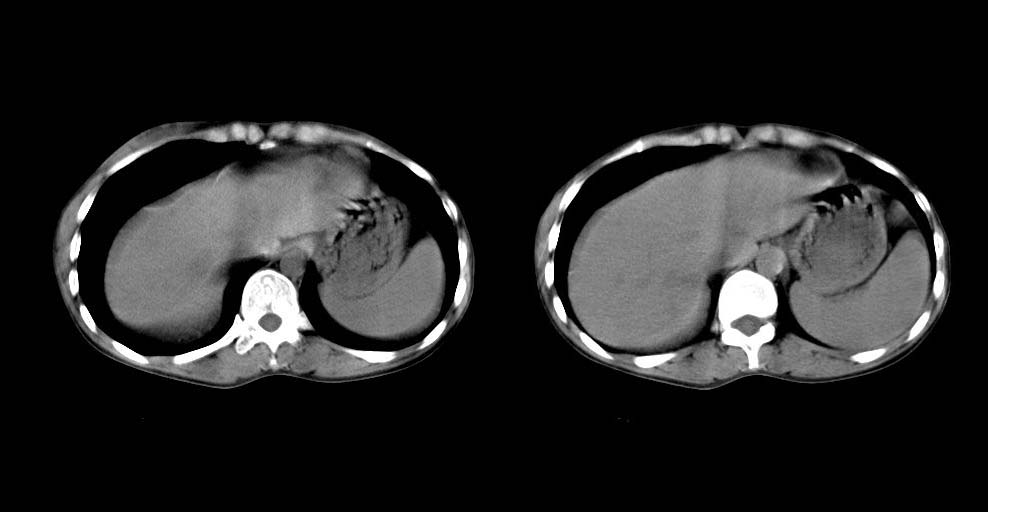

病人资料:女 30岁 右上腹部疼6天余.无其他不适,我院血常规正常,胸片正常,b超示1,肝内多发性结石.2,肝实质内似见结节影,占位病变待定.

2、肝胆胰脾ct平扫未见明显异常肿块影。

平扫不能说明什么,血管断面也可以啊!!建议增强,肝脏不增强的没有什么意义!!

建议增强检查,平扫也显示脾肿大。